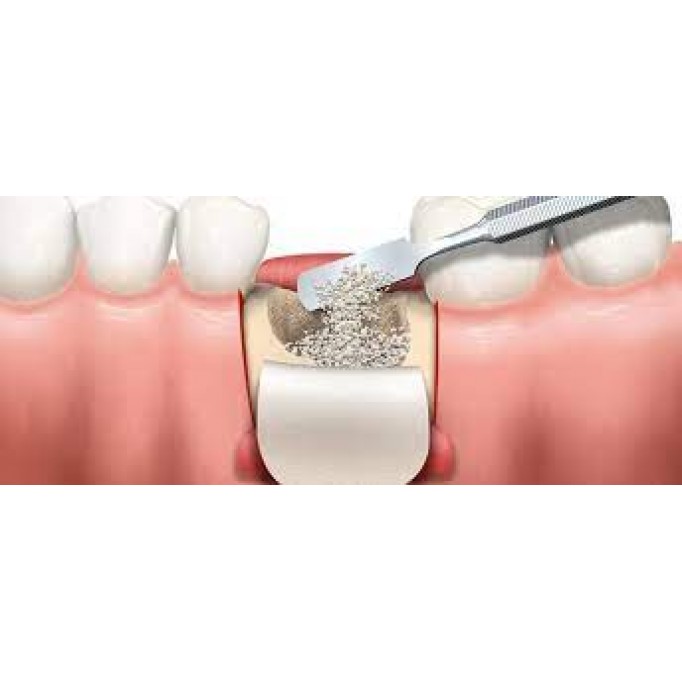

Нарощування кісткової тканини перед імплантацієюОпис:Нарощування кісткової тканини — це важлива проц..

Види і технології проведення кісткової пластикиКісткову пластику зуба проводять за кількома технолог..

Як довго триває кісткова пластика?Кісткова пластика займає від 60 до 120 хвилин і виконується під мі..